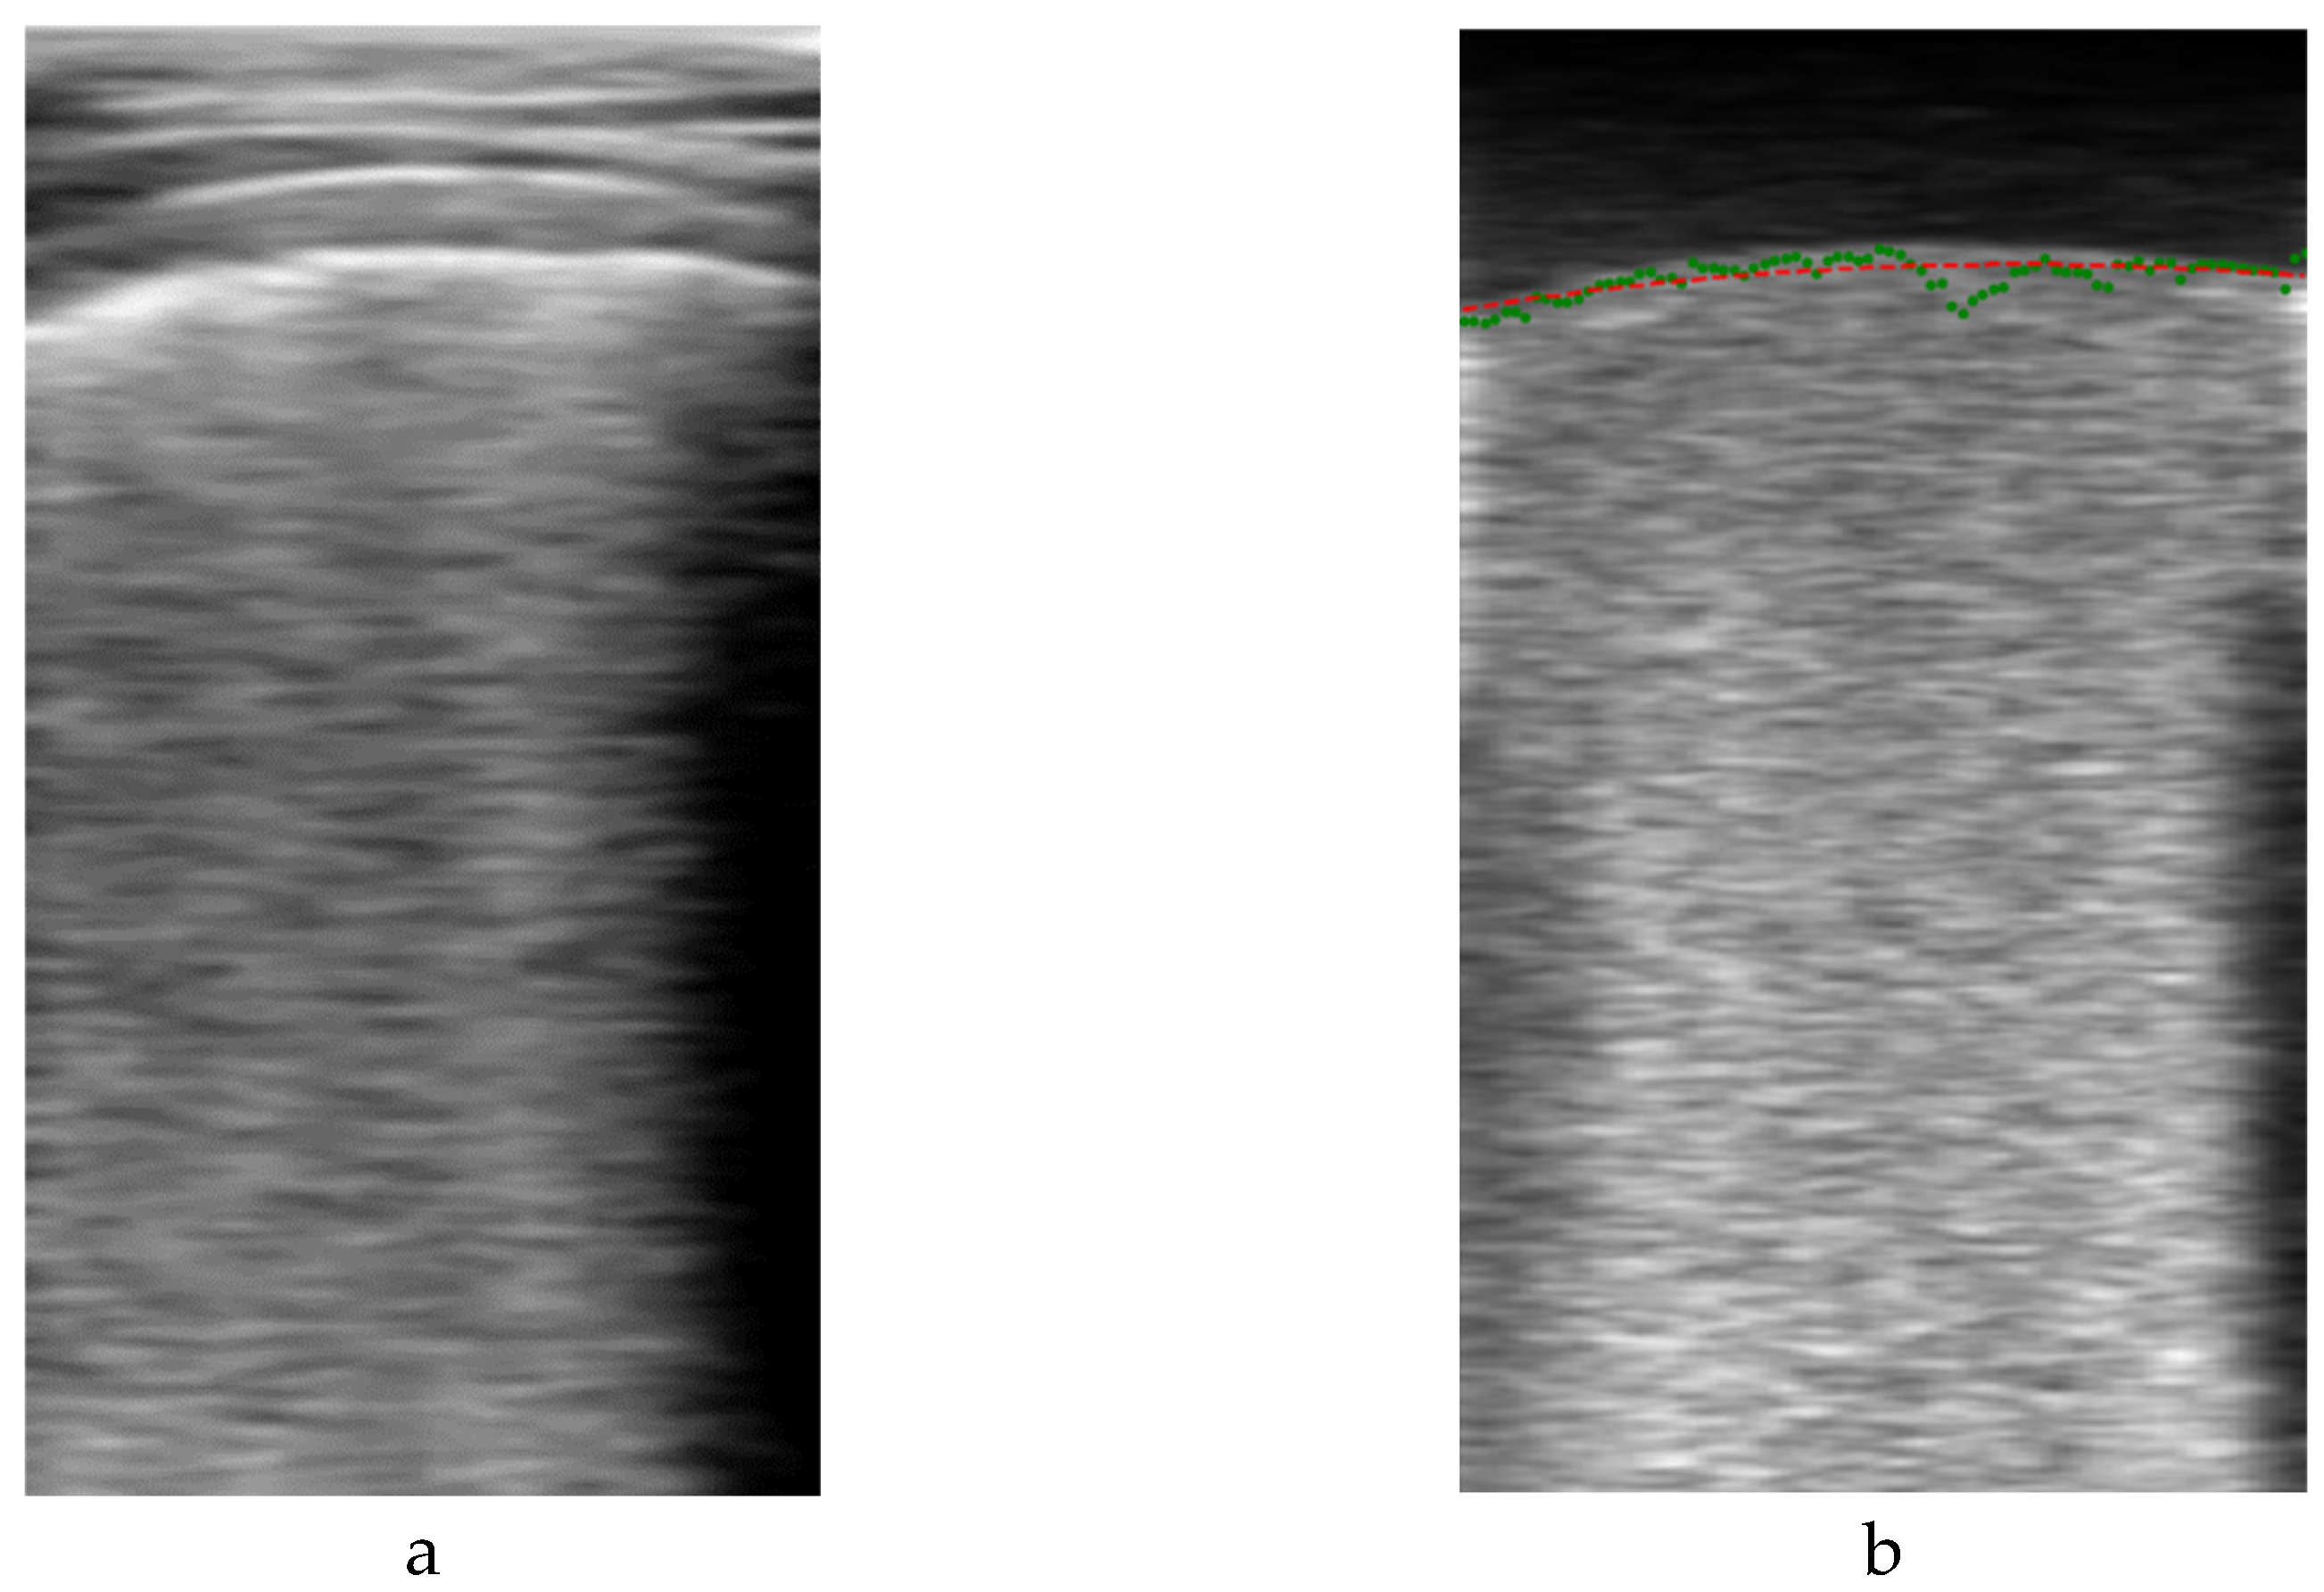

2.4.1.1. Pleural Line Labelling

One of the most important indications to identify in a lung ultrasound image is the pleura, because it defines the zone where the artifacts have to be looked for. Correctly identifying the pleura helps to discard zones that do not have to be analyzed, like the ribs and their shadows and the muscle and fat area above it. Giving this information to the neural network could improve the results, as it will learn that the B-Lines and consolidations are located bellow the pleura, and not in other areas of the image.

The algorithm for automatically segmenting the pleura is based on the fact that, when the ultrasound probe remains stationary, the image above the pleura (fat and muscle) remains basically unchanged between frames, while variations in the image occur below the pleura due to the respiratory cycle. Then, by subtracting consecutive frames, an auxiliary image is formed, where the upper region is almost black, and the lower part is bright. Furthermore, if several of these images are averaged, the random nature of the speckle in the lower part generates a quite homogeneous region that can be more easily distinguished from the upper region. The frontier between these regions can be considered a first approximation of the pleura line.

being L the length of the averaging filter. Figure 4 shows an example output of the algorithm. On the left is the original Bi image of a frame, and on the right its filtered version Vi, showing the two formerly mentioned dark and bright zones. For detecting their boundary, a dynamic threshold was applied to each vertical line of the filtered image, calculated from the average amplitude of the upper part of the image:

P ~ j = m i n i |   A j i > t h j

where A j is the vertical line of the filtered image at column j, P ~ j is the vertical index to the pleura guess for that line and thj the applied threshold. Figure 4.b shows with green dots an example of this set of initial pleura raw guess points P ~ n , which are then used to fit a second order polynomial to obtain a smooth representation P n of the initial guess (red line in Figure 4.b).

It is worth to mention that directly applying a threshold to the original image (Figure 4.a) is very prone to misdetections, as other horizontal bright lines in the upper region of the image are present, with pixel intensity values even larger than those of the pleura. On the other hand, the auxiliary image filtered by the proposed method is very suitable for a simple threshold detection, because of its stepped nature.

Figure 4. First pleura approximation example. a) original B-scan image; b) filtered image.